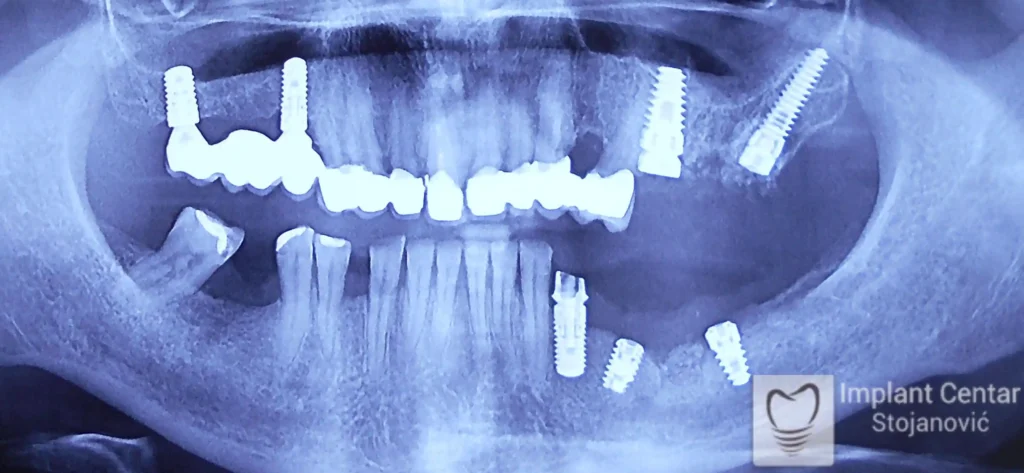

Pacijentkinja je došla sa dotrajalim mostovima i preostalim zubima loše biološke vrednosti, dok su bezubi prostori bili prisutni u gornjoj vilici sa desne strane i  u donjoj vilici sa leve strane. Nakon detaljnog kliničkog pregleda i analize snimaka, izvršeno je vađenje svih zuba i ugradnja optimalnog broja dentalnih implantata.

Već tri dana nakon operacije pacijentkinja je zbrinuta privremenim krunicama, kojima je bila oduševljena jer su odmah omogućile funkciju i estetiku. Nakon perioda oseointegracije izrađene su definitivne cirkonijum-keramičke krunice, čime je postignuta maksimalna estetika, funkcija i vraćeno samopouzdanje. Pacijentkinja je presrećna postignutim rezultatom.